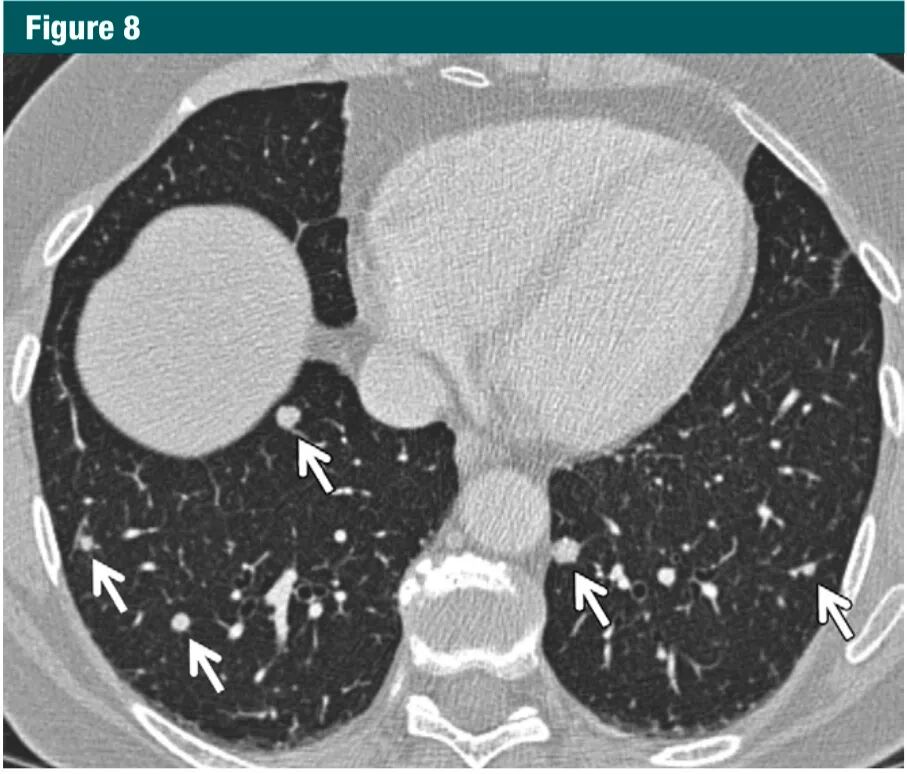

对于多发实性非钙化结节且至少有一个结节≥6mm,建议大约 3-6 个月随访,之后根据风险评估可选择二次随访,在 18-24 个月(1B级:强烈推荐,中等质量证据)。如果更大的结节或更可疑的结节存在,应采用针对孤立结节的指南进行处理,如前述。在这种情形下, 转移瘤仍是首要考虑的,特别是结节分布呈外周性和/或下叶为主,且结节大小不等(图8)。在大多数病例中,转移灶将在 3 个月内有可见的生长。NELSON研究中一项有关多结节的分析表明,随着结节总数从 1 增加到 4 个时,原发癌的风险增高;但 5 个或更多结节的风险反而会降低,因为大多是之前肉芽肿感染导致的。

图片

图8.CT图像显示大小不等的多发实性结节,以下野为主(箭头)。甲状腺癌肺转移7Gc帝国网站管理系统